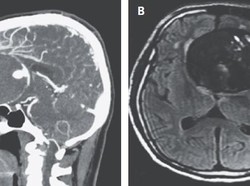

Stroke sering disebut silent killer. Pasien sering terlambat mendapatkan pertolongan karena stroke tak memiliki gejala khusus.